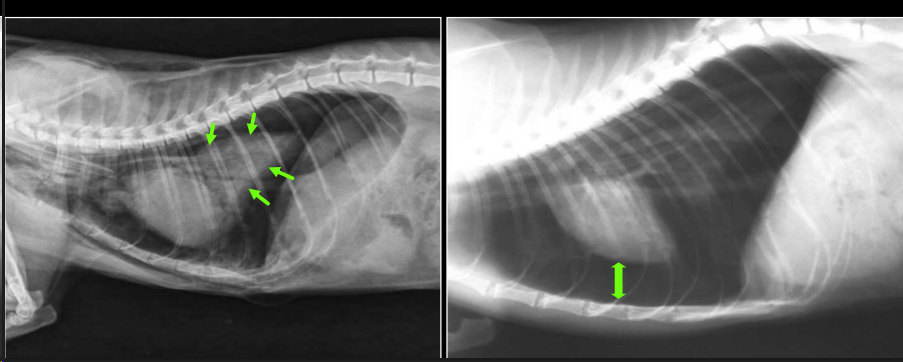

INSPIRACIÓN Y ESPIRACIÓN

Inspiración:

- Diafragma por detrás de T11.

- Aumenta la distancia entre silueta cardíaca y diafragma.

- Los lóbulos pulmonares parecen mayores.

- Los pulmones parecen más radiolúcidos.

Espiración:

- Diafragma por delante de T11.

- Diafragma y silueta cardíaca más próximos.

- Los pulmones parecen más radioopacos.

Disparo: pico de máxima inspiración.